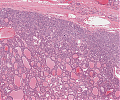

Follikuläres_NHL_A96.png

Lymphomgewebe mit Proliferation unreifer Zentroblasten und Zentrozyten

A52 Hodgkin-Lymphom

Mehrkernige Reed-Sternberg Zelle mit mit prominenten Nukleoli beim klassischen Hodgkin-Lymphom.